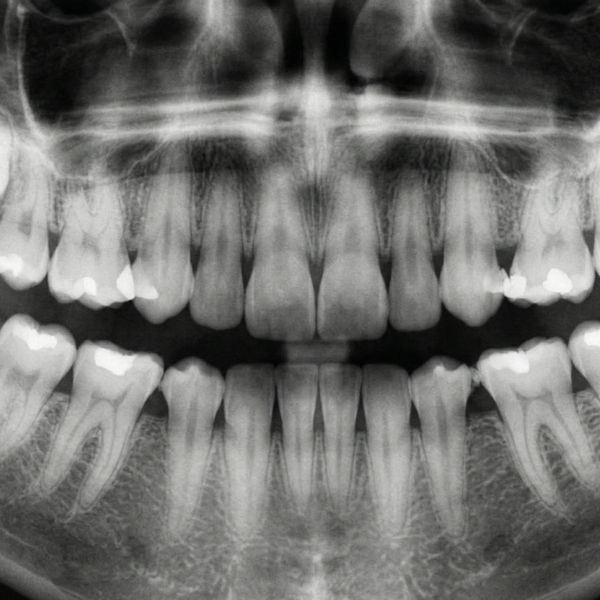

Your mouth is a primary entryway to your entire body. When a tooth is severely decayed or damaged, it creates a potential vulnerability where harmful bacteria can easily enter your bloodstream, potentially increasing the risk of serious systemic issues like cardiovascular disease or infection. By repairing these weaknesses through restorative solutions, we effectively protect your body from this unwanted bacterial invasion.

When a tooth is lost, the immediate surrounding teeth will naturally begin to shift and drift into that empty gap, destabilizing your entire bite structure. This subsequent movement often results in improper misalignment, significantly difficulty cleaning, and eventually causes painful temporomandibular joint (TMJ) disorders. Restoring those gaps with durable crowns, bridges, or modern dental implants preserves proper dental alignment and long-term oral stability.

Preserving Critical Jawbone Structure

Healthy, living teeth provide the continuous and vital stimulation your jawbone requires to maintain its essential strength and density. Following adult tooth loss, the supporting bone quickly begins to deteriorate or reabsorb, often leading to a potentially aged, gaunt facial structure. We effectively address this by utilizing dental implants, which mimic the vital natural root structure, providing that essential stimulation that keeps your jawbone strong, healthy, and functional.